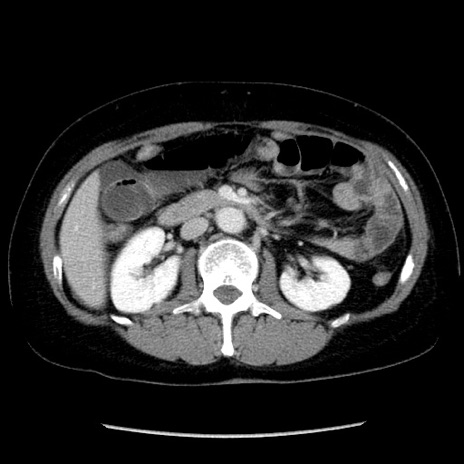

冠状断像

【症例】50歳代女性

【主訴】下腹部痛

【現病歴】本日朝より下痢2回あり。 昼食を食べた後、嘔吐3回、下腹部痛認め、症状軽快せず、当院救急搬送。

最終食事:本日昼(生ものなし)。 昨日の夜、刺身を食ぺたとのこと。周囲に同様の症状の者なし。普段、排便は毎日あるとのこと。

【既往歴】卵巣癌術後(8年前に当院で卵巣摘出)

【身体所見】 意識清明、腹部:平坦、腸蠕動音→、やや硬、下腹部自発痛・圧痛あり、反跳痛あり、筋性防御なし。

【データ】WBC 16000、CRP 0.01